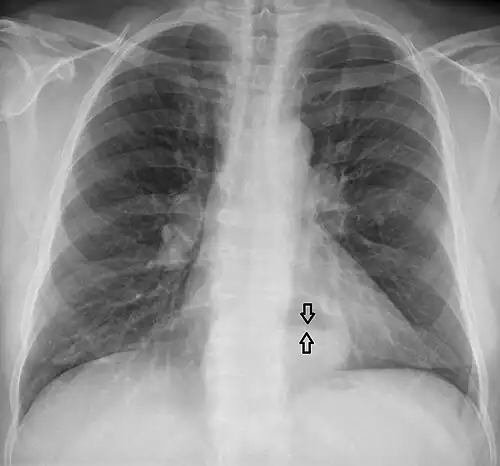

A large hiatal hernia on chest X-ray marked by open arrows in contrast to the heart borders marked by closed arrows